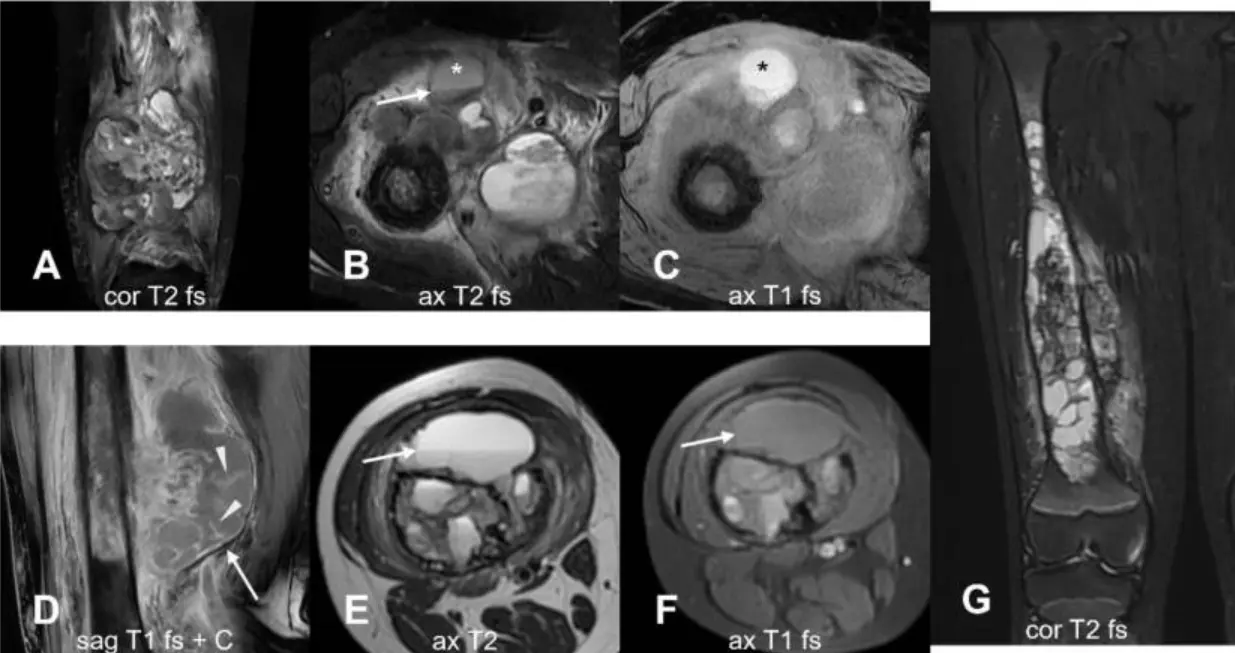

MRI is highly effective for evaluating bone cancer because it precisely shows the length and volume of the tumour, including how far it spreads inside the bone marrow (intramedullary spread) and whether it extends into nearby soft tissues26. This accuracy is crucial for planning limb-sparing surgeries, as MRI measurements of tumour boundaries closely correlate with what is found during surgery, allowing surgeons to determine safe margins for removing the tumour. MRI is also superior to other imaging methods for detecting subtle or early bone lesions, especially when radiographs or CT scans are inconclusive2,4.

In addition to mapping tumour size, MRI can distinguish between cortical destruction and an intact but thinned cortex, which is key for surgical decision-making26. It also shows the tumour’s relationship to important structures, such as nerves, blood vessels, and the joint capsule, helping surgeons avoid critical areas and achieve clear margins. MRI can detect periosteal reactions, such as laminated, sunburst, or Codman triangle patterns, that suggest tumour grade and aggressiveness, with diagnostic performance comparable to conventional radiography21.

MRI further shows soft tissue oedema (swelling) and areas of diffusion restriction (low ADC values), which indicate high tumour cell density and help differentiate malignant from benign lesions27. These imaging features not only guide diagnosis but also allow for monitoring how well the tumour responds to treatments, such as chemotherapy, by tracking changes in marrow signal and the percentage of tumour necrosis2.